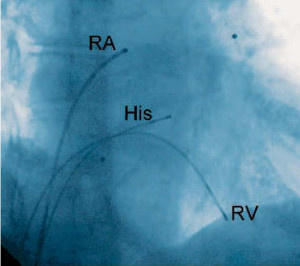

Bei der elektrophysiologischen Untersuchung werden typischerweise drei weiche Elektrodenkatheter im Herz platziert.

RA = rechtes Atrium (Vorhof)

His = AV-Knoten-Region (am His-Bündel)

RV = rechter Ventrikel (Hauptkammer)